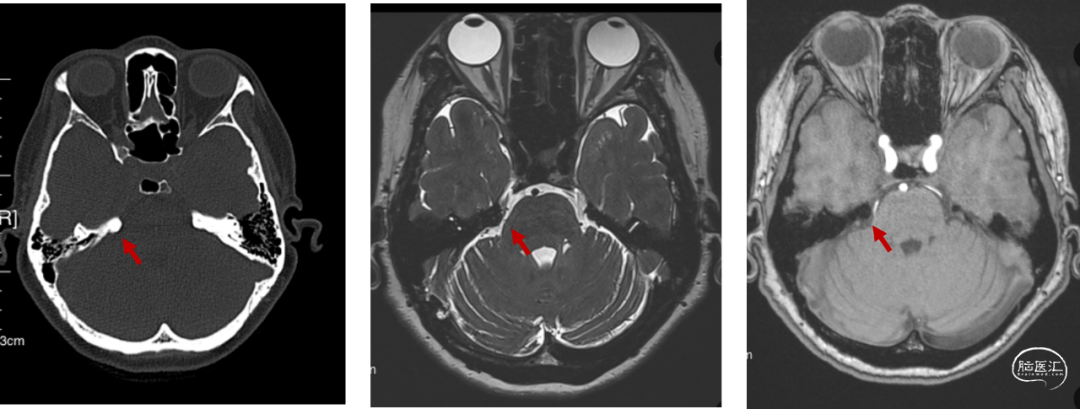

红色箭头显示为凸起的岩骨嵴